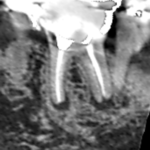

下顎第二小臼歯と第一大臼歯の初診時のCT画像です。

下顎第二小臼歯と第一大臼歯の根の先に膿の影がみられました。第一大臼歯は、2本ある根の両方に膿がみられます。